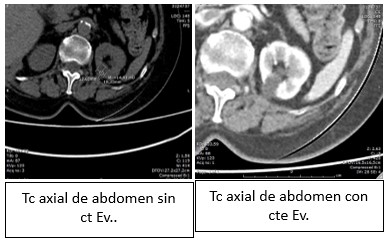

La Categoría I define la lesión como densidad agua (0-20 UH), sin septos o calcificaciones, ausencia de polos sólidos y sin realce a la administración de medio de contraste yodado IV.(19, 20) Su clasificación sería de quiste simple benigno y no requeriría ningún tipo de evaluación posterior. Son lesiones asintomáticas que rara vez requieren tratamiento. No es necesario realizar controles posteriores (Anexos 3 y 4).

- Bosniak I: el 80% de los quistes (418 pacientes) fueron clasificados como Bosniak I, es decir, quistes simples hallados incidentalmente en tomografía computada (TC) y sin necesidad de seguimiento adicional. De estos, 268 pacientes eran de sexo masculino y 150 de sexo femenino (Anexos 17 y 18).